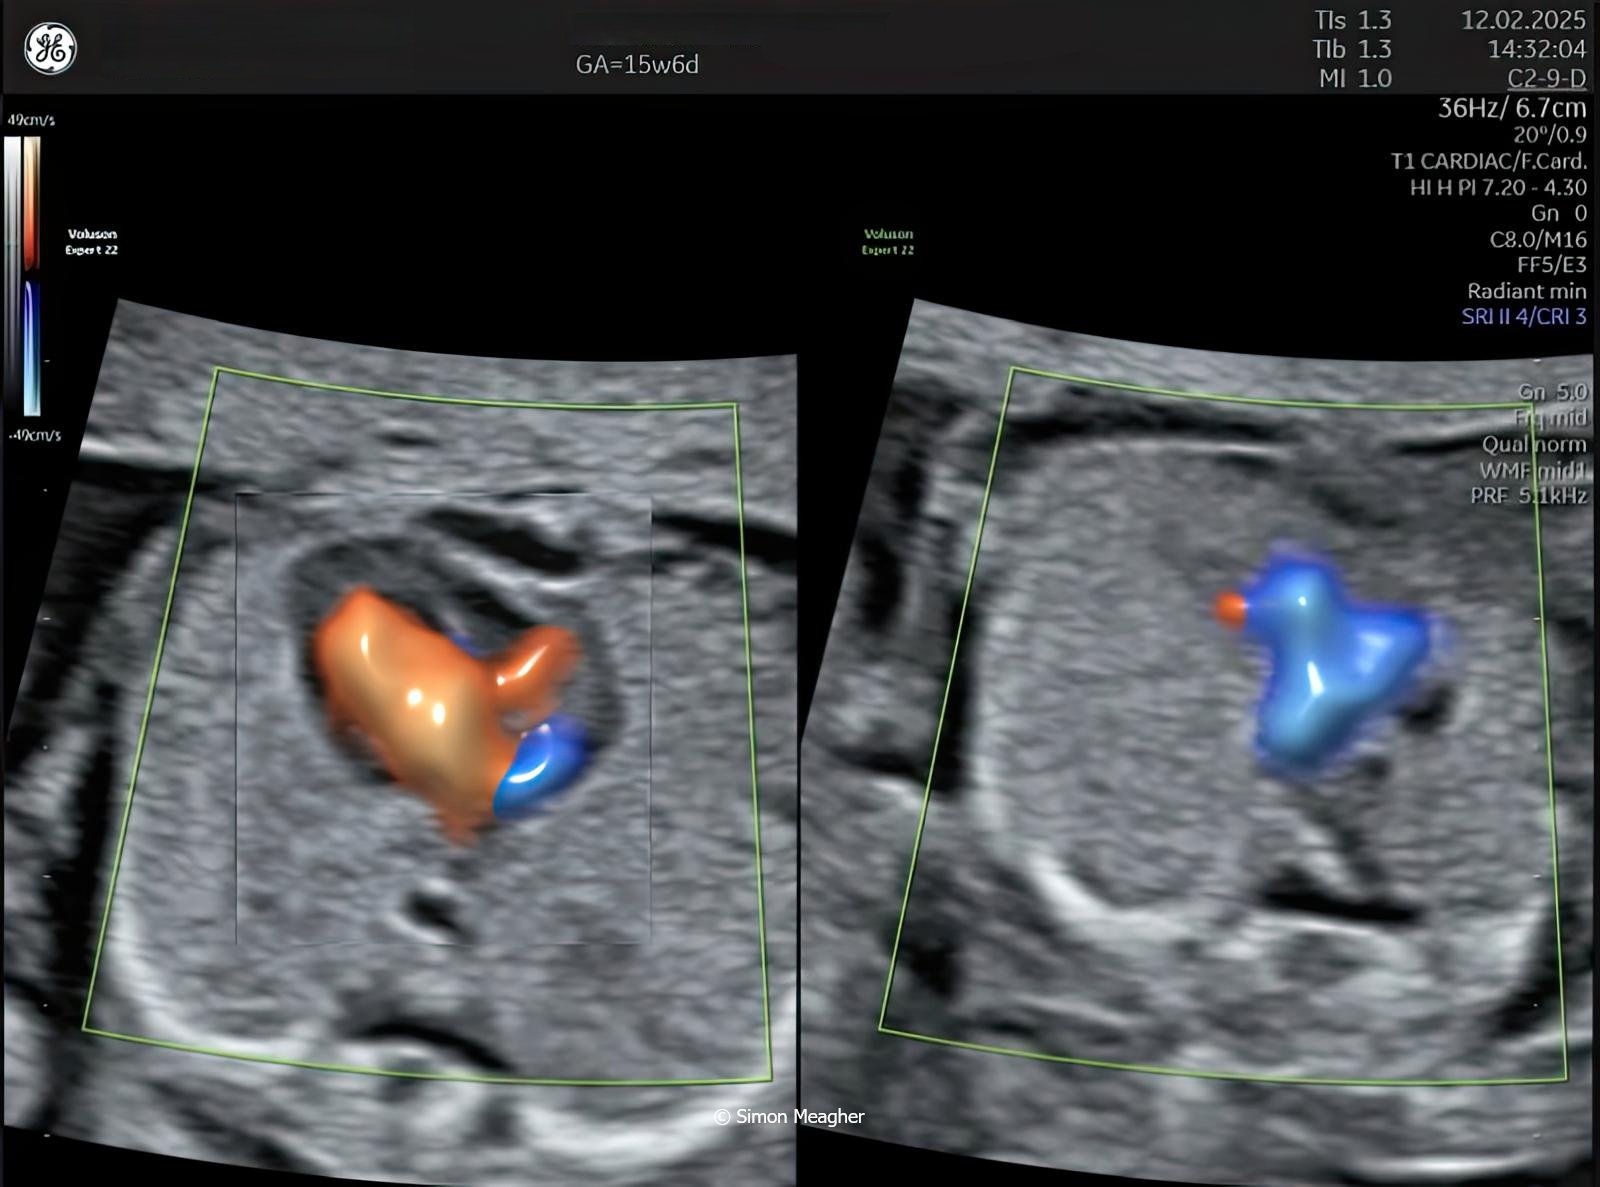

Join Professor Simon Meagher and leading experts for an intensive masterclass designed to transform your clinical practice.

This high-impact, one-day event delivers live scanning demonstrations, real-world case studies, and cutting-edge techniques across all trimesters.